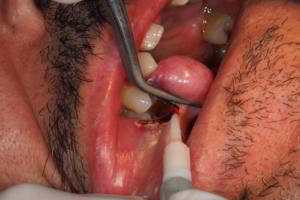

· Imagen 20, leer más...

Los injertos de tejido conectivo autólogo obtenidos del paladar son una satisfactoria vía de tratamiento de las retracciones gingivales localizadas, frecuentemente, en el sector anterior. Se otorga de esta forma un sustento gingival y cobertura de la exposición radicular de los dientes afectados mejorando su salud periodontal.